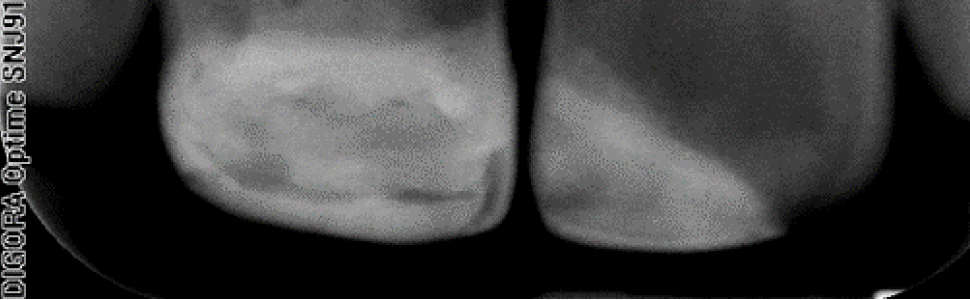

Rewaskularyzacja jest stosunkowo nową metodą postępowania w leczeniu martwicy miazgi i (lub) zapaleń tkanek okołowierzchołkowych w zębach stałych z niezakończonym rozwojem wierzchołka korzenia. Polega na usunięciu chorobowo zmienionej tkanki i stworzeniu warunków do zastąpienia jej nową tkanką miazgopodobną (1, 2). Metoda ta pozwala na zachowanie funkcji zęba, pogrubienie ścian korzenia i zakończenie formowania się wierzchołka zęba.

Revascularization is a relatively new method of treatment management of pulp necrosis and (or) periapical inflammation in permanent teeth with unfinished root development. It consists in removing the diseased tissue and creating conditions for replacing it with a new pulp like tissue (1, 2). The method allows to preserve the tooth function, thickening the root walls and completing the formation of the tooth apex.